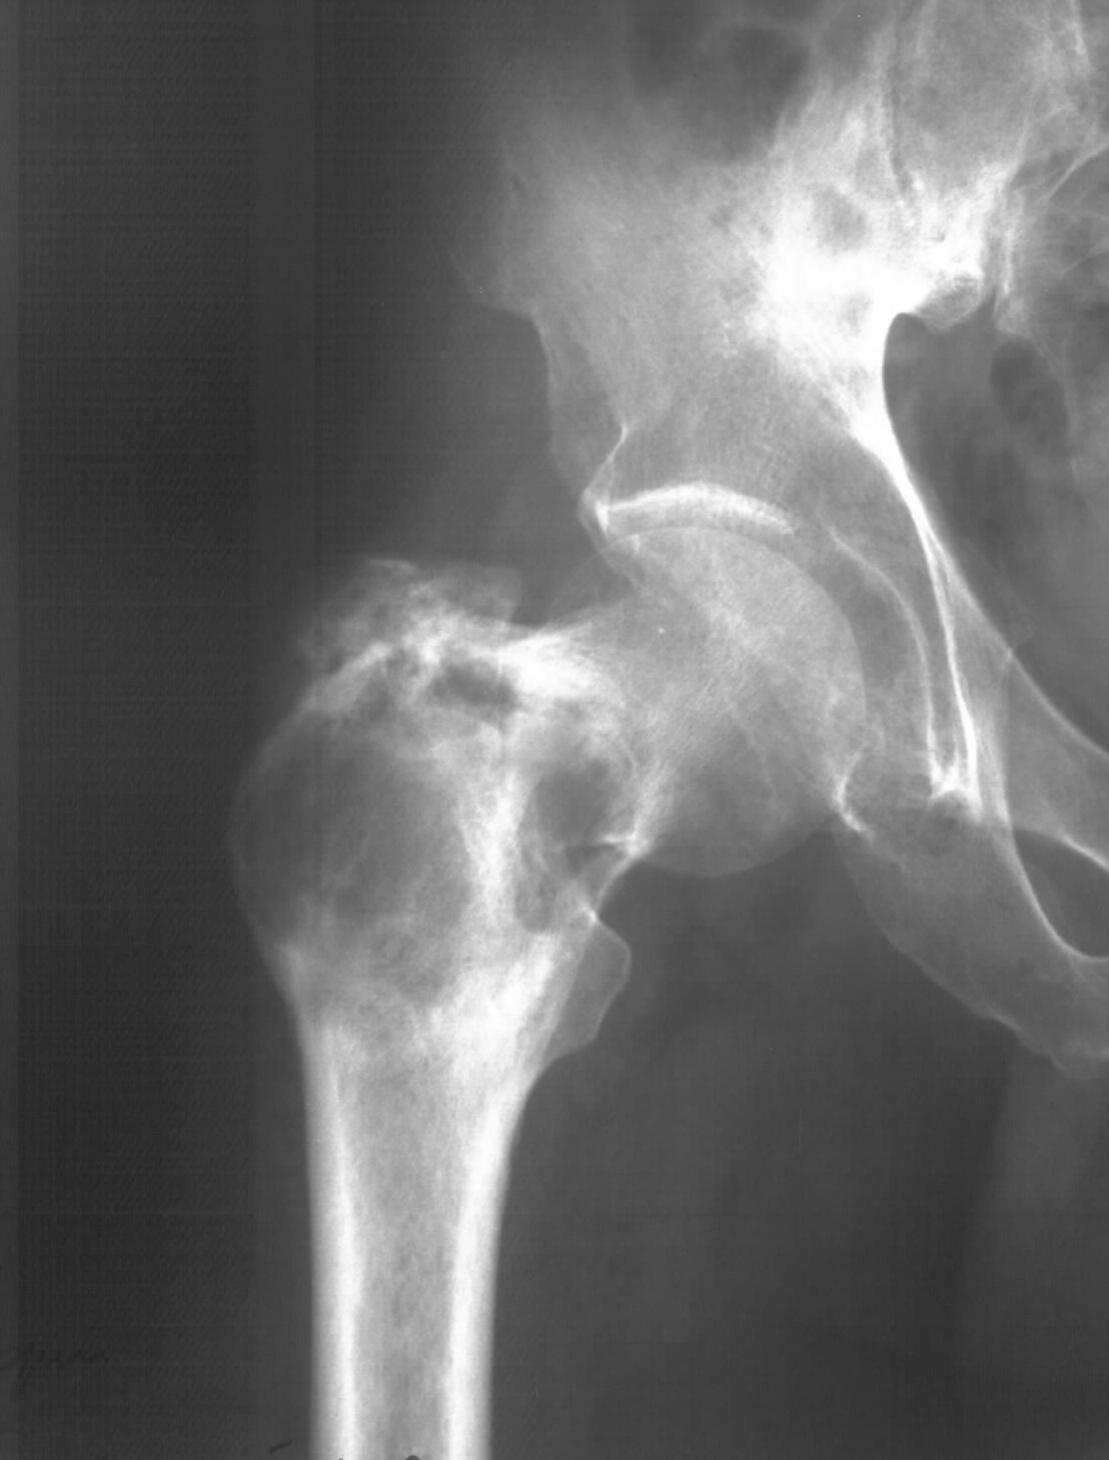

Диагноз: Ангиосаркома проксимального отдела правой бедренной кости. Патологический перелом шейки бедренной кости. Множественные метастазы в легкие, позвоночник, ребра, кости таза.

Считает себя больным с 2005 года, когда впервые появились боли в правом тазобедренном суставе с иррадиацией в поясничную область. Лечился по месту жительства по поводу поясничного остеохондроза, люмбоишиалгии. Отмечает постепенное усиление болей в области правого тазобедренного сустава. С августа 2007 года появилась хромота. В 2008 году была выполнена рентгенография тазобедренного сустава, выявлен патологический очаг в проксимальном отделе бедренной кости. Консультирован онкологом. Обследовался стационарно в травматолого-ортопедическом отделении №1 ГУЗ «СККЦ СВМП». Была выполнена операционная биопсия. Заключение: «наиболее вероятна картина гемангиоэндотелиомы с явлениями пролиферации и атипии». Для дальнейшего лечения был направлен в РОНЦ им. Н.Н.Блохина РАМН. Повторно была выполнена операционная биопсия с иммуногистохимическим исследованием материала. Заключение: «морфологическая картина более всего соответствует ангиосаркоме». Получил курс лучевой терапии. Планировалась повторная госпитализация для органосохраняющего оперативного лечения. Однако до настоящего времени госпитализация не состоялась.

31.05.09 упал дома с высоты собственного роста. Появились сильные боли в правом тазобедренном суставе. Самостоятельно обратился в ГУЗ «СККЦ СВМП». При клиническом обследовании и рентгенографии был диагностирован патологический перелом шейки бедренной кости.Объективно:

Интересно как онкологи оценивают вероятную подолжительность жизни, если более полугода, то наверное можно предложить биполярный онкологический протез. Для обсуждения не хватает снимков бедра на всю длину, и более подробной КТ ацетабулюма.

По этому пациенту тактика, видимо, должна зависеть от онкологического прогноза. Если онкологи оценивают ожидаемую продолжительность жизни больше 2-3 лет, то ориентировааться на онкологический протез с резекцией очага. Если прогноз хуже, то сделать остеосинтез гамма гвоздем без вмешательства на очаге.

Судя по КТ опухоль кроме шейки захватила большой трохантер и частично головку бедра. На мой взгляд, даже самое удачное расположенние винтов гвоздя не позволит больному полностью наступать на ногу. Протез же позволит больному максимально улучшить качество оставшейся жизни с раннего послеоперационного периода.

2.Все варианты остеосинтеза представляются нецелесообразными - мы имеем "скорлупу" в проксимальном отделе бедра (к чему там винтиться?);

3. Если уж оперировать, то, конечно же - онкологический эндопротез.

В данном случае рациональным был бы онкопротез (ИМХО), гвоздик не даст "нормальной функции".